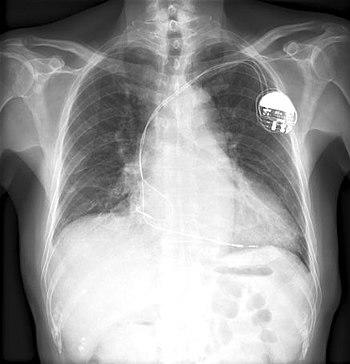

(CardioNetworks ECGpedia)

A chest x-ray of a pacemaker

Boykin patented as many as 26 devices.[12] He is best known for inventing electronic control devices for guided missiles, IBM computers, and the pacemaker. [13] One of his early inventions was an improved wire resistor, which had reduced inductance and reactance, due to the physical arrangement of the wire.[14] Other notable inventions include a variable resistor used in guided missiles.[15] His most famous invention was likely a control unit for the artificial cardiac pacemaker.[4] The device essentially uses electrical impulses to maintain a regular heartbeat. Among his other inventions is a burglar-proof cash register.[16] Boykin died in Chicago on March 26, 1982, at the age of 61.[3]